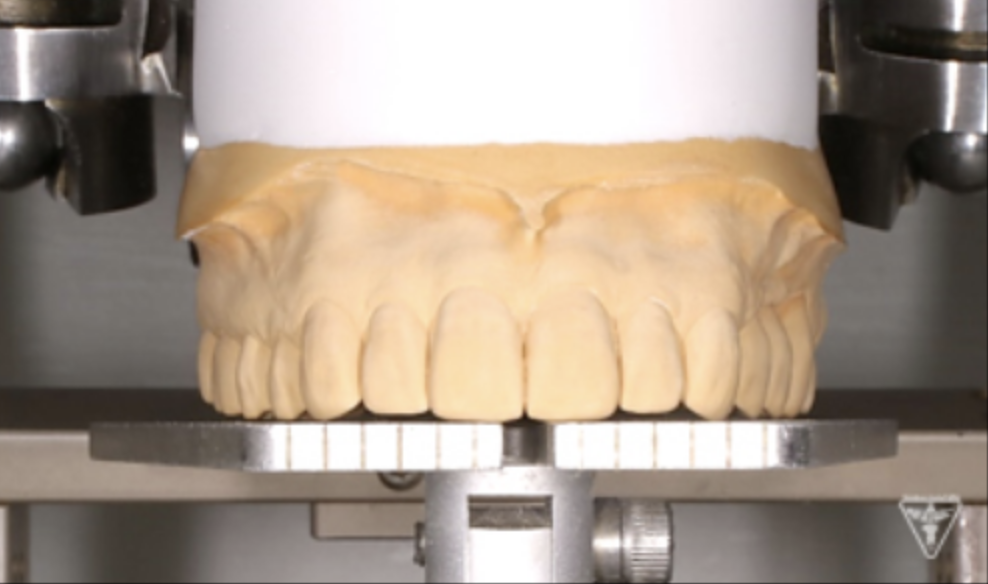

咬合調整

粉砕効率の高い小さな点による均衝接触をつくります。

咬合様式は、ミューチャリープロテクトオクルージョンを付与しました。

咬合平面の評価(SHILLAⅡの平面板による)